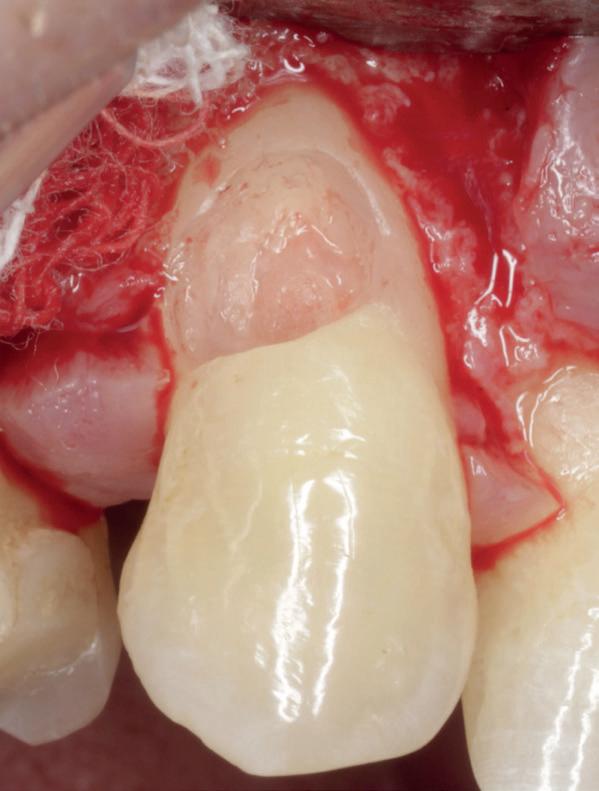

Het isoleren van het werkgebied is belangrijk. Op deze manier krijgt de behandelaar meer controle over het werkgebied en is werken onder microscopisch zicht mogelijk. Eventueel kan er gebruik gemaakt worden van de ‘split dam techniek’, zodat het subgingivale gebied toegankelijker is. Het (opnieuw) plaatsen van het cofferdamvel na preparatie is ook een mogelijkheid (afbeelding 1 en 2).

Stap 2: Preparatie van element en gingiva

Verwijder carieus tandweefsel en maak bij twijfel gebruik van een cariësdetector. In veel gevallen zal het voorkomen dat je subgingivaal eindigt. Gingiva dat in de preparatie ligt kun je verwijderen met bijvoorbeeld een elektrotoom. Ikzelf maak gebruik van

een draadloze warmtespreader, de Superendo Alpha (afbeelding 3 en 4).